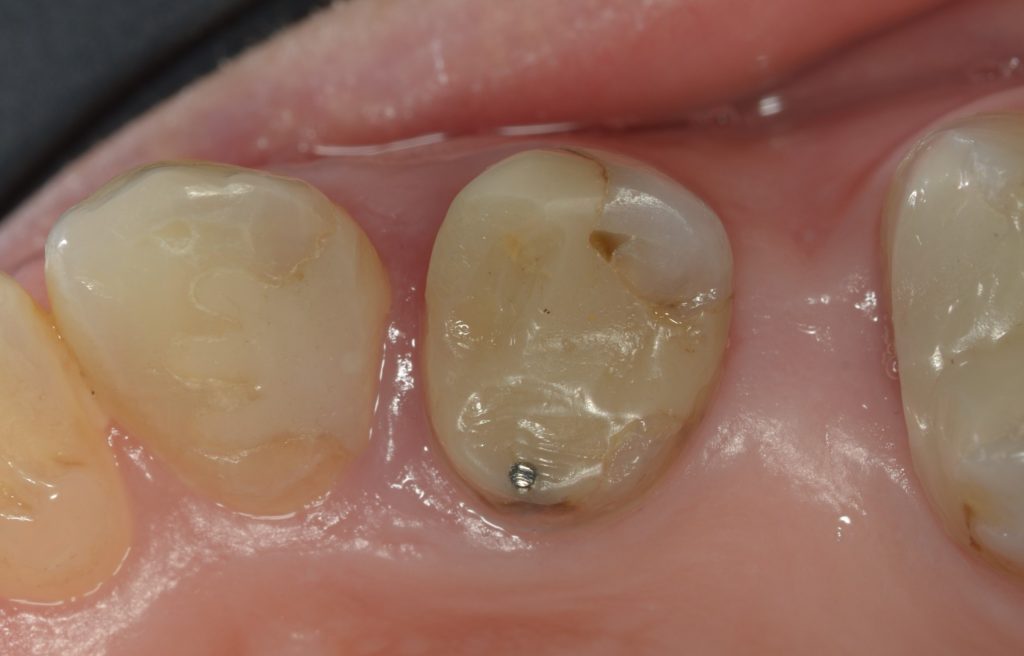

It has been years since I prepped below the height of contour and invaded the biorim, but here we are back at Day 0. By the time I removed caries and old composite and reduced the thin lingual cusps, all that was left was connecting the margins at the line angle. I’ll be honest, for a split second, I thought about filling in all the defects with direct composite, but I did not because I was running late.